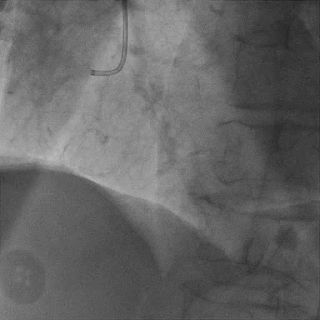

双侧造影,观察闭塞起始位置、长度、走行等

尝试通过RCA-圆锥支侧枝逆向开通LAD :

微导管辅助下,用SUOH03导丝尝试送入侧枝

经微导管TIP injection可见侧枝重度迂曲

侧枝重度迂曲,反复尝试未能通过